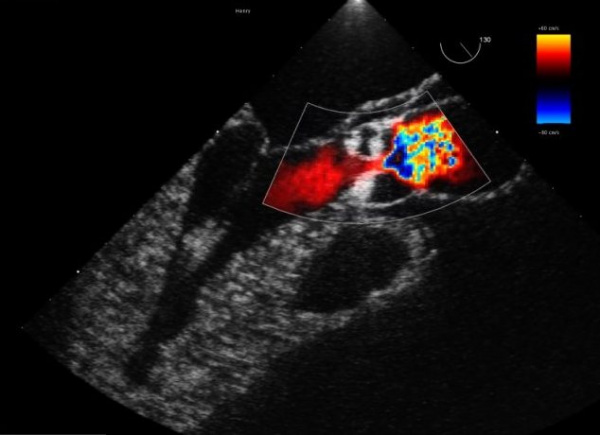

Двухмерная эхокардиография, проведенная из супрастернального доступа, обнаруживает коарктацию аорты в виде ярких эхосигналов в просвете аорты, увеличение правого предсердия и желудочка. Доплерэхокардиография позволяет выявить ускоренный турбулентный поток крови за местом стеноза.